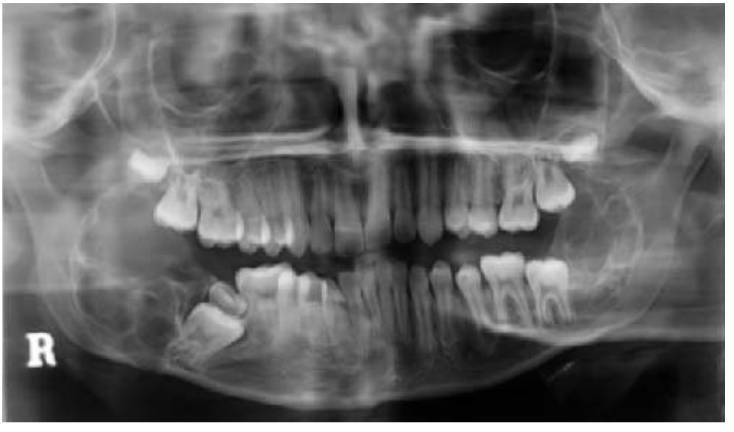

Los dientes supernumerarios surgen como resultado de una geminación de la lámina dental que se produce de forma esporádica o se heredan, como sucede con la displasia cleidocraneal (fig. 9.8).

- Erupción fallida o ectópica de un diente permanente (fig. 9.8B).

- Como parte de un síndrome, como la displasia cleidocraneal (fig. 9.9).